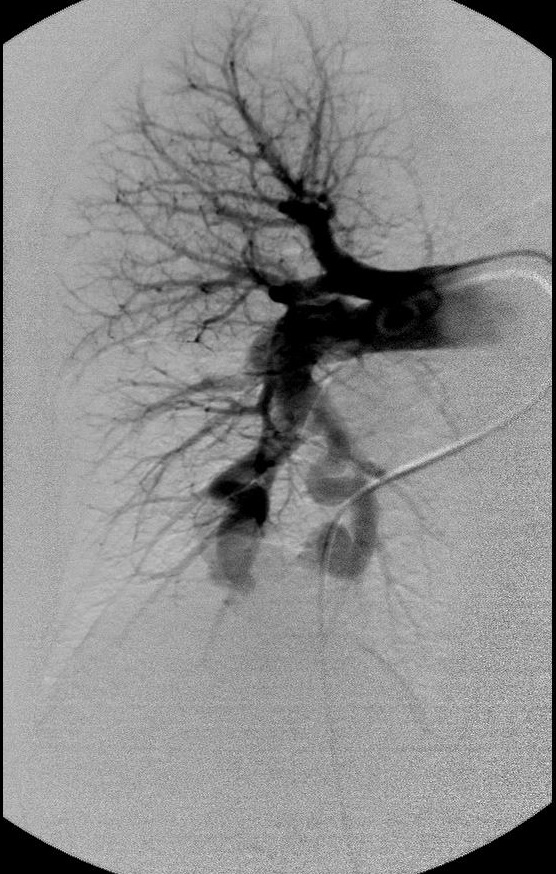

肺动静脉畸形

|

|

|

肺动静脉畸形分为单发、多发和弥漫性 |

这一例为多发性肺动静脉畸形 |

|

|

|

显示巨大静脉池显影 |

回流至肺静脉 |